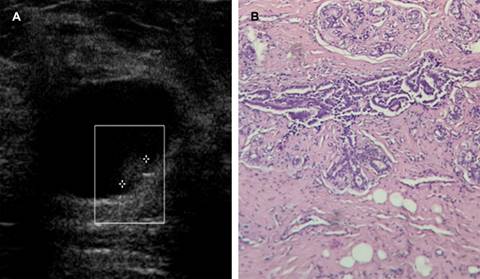

Las lesiones papilares constituyen un conjunto de entidades caracterizadas por una proliferación epitelial que asienta sobre ejes fibrovasculares en su presentación clínica habitual (Figura 2).5

Figura 2: Papiloma intraductal. A) Ultrasonográficamente se observa un quiste complejo con una imagen nodular de morfología irregular sólida interna. B) Histopatológicamente con proyecciones papilares y un centro revestido por células epiteliales y mioepiteliales que ocupan la luz dilatada de un ducto.

La papilomatosis múltiple, que es una entidad poco frecuente, se ha asociado a un potencial premaligno. Se caracteriza por la presencia de proyecciones papilares con un centro revestido por células epiteliales y mioepiteliales que ocupan la luz dilatada de los ductos terminales (Figura 2B).6